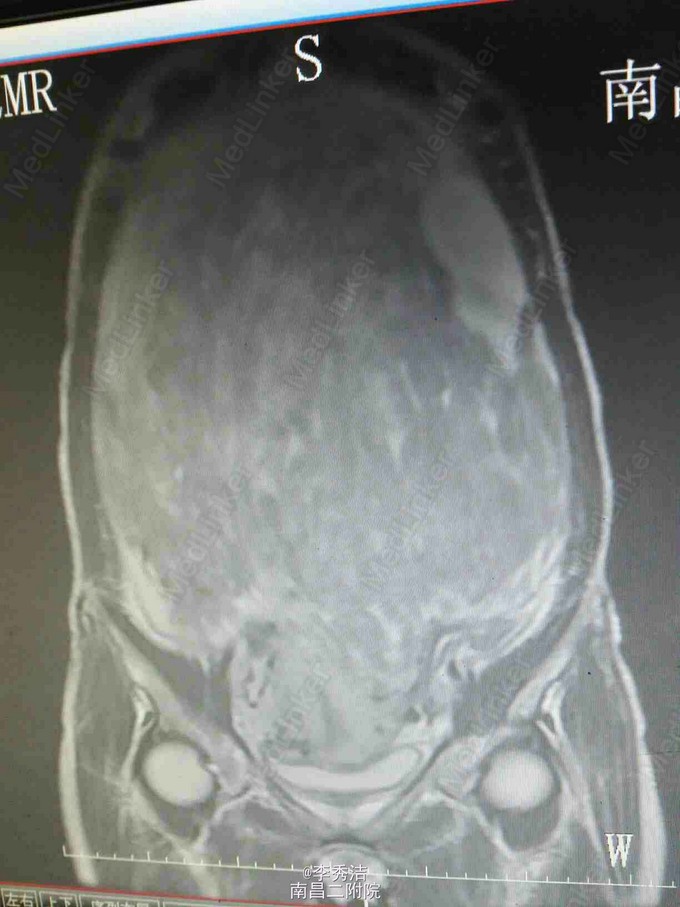

妇科检查:子宫孕9月大小,无压痛,活动。彩超示:子宫体积明显增大,内部呈蜂窝状考虑子宫肌瘤癌变,双侧附件区显示不清。腹部ct示:盆腹腔巨大肿块,子宫及双侧附件显示不清。

行剖腹探查术,术中见子宫血管显露,子宫底部触及一大小约35*30*12cm肌瘤样囊性包块,占据盆腹腔大部分,质软,表面光滑,充满手术野,包块与盆腔后壁肠系膜膜性粘连,右侧卵巢见一直径约5cm囊性包块,表面光滑。松解粘连后,行子宫肌瘤剔除术+右侧卵巢囊肿剔除术,剔除肌瘤16Kg。术中冰冻切片示:(子宫)初步考虑平滑肌瘤伴出血、变性。右侧卵巢良性囊性病变。诊断为1.子宫肌瘤变性,2.右侧卵巢囊肿。